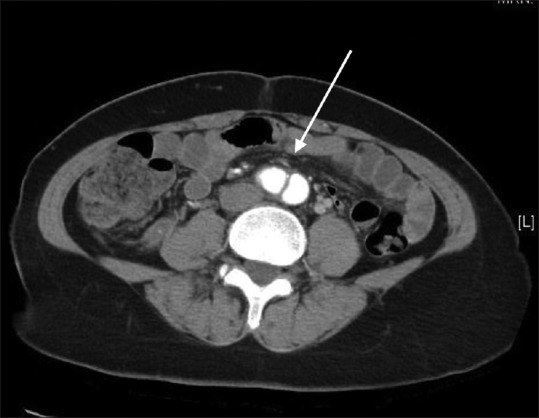

Isolated pelvic pain caused by aortic dissection is a very uncommon clinical presentation. This life-threatening cardiovascular lesion needs prompt diagnosis and intervention to prevent rupture. We report the case of a 45-year-old woman with Marfan syndrome who presented to our gynecologic clinic with low abdominal pain. Bedside point-of-care ultrasound revealed the bilocular echo lucent cystic lesion indicating the dissection of common iliac artery in her pelvis.

由主动脉夹层引起的孤立性骨盆疼痛是一种非常罕见的临床表现。这种危及生命的心血管病变需要及时诊断和干预,以防止破裂。我们报告的情况下,45岁的妇女马凡氏综合征谁提出了我们的妇科门诊下腹痛。床边超声显示双腔回声清晰的囊性病变,提示骨盆髂总动脉夹层。